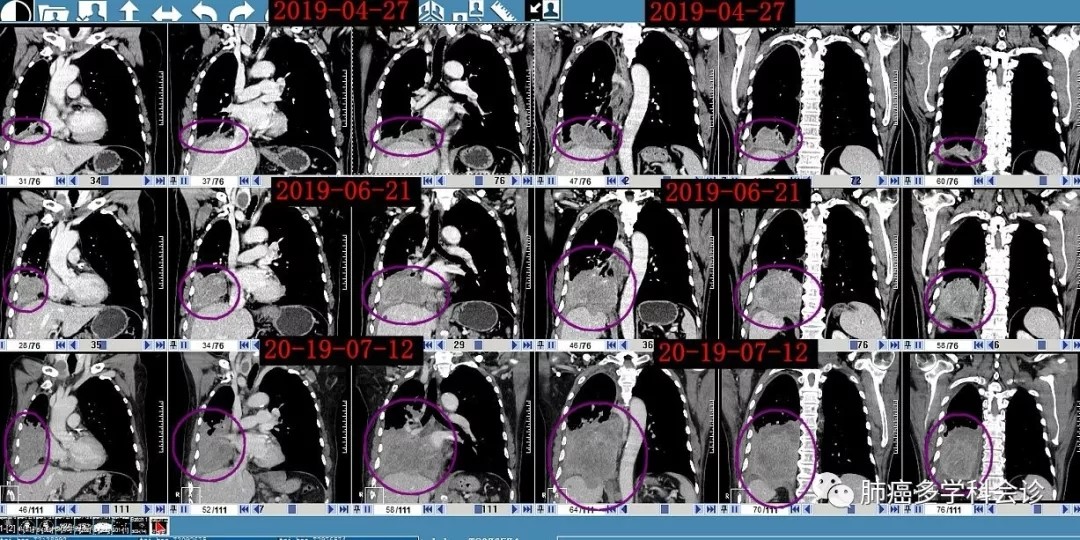

2019-4-25 复查头颅MRI:左侧顶颞叶、左侧小脑半球异常强化灶,结合病史,考虑转移。2019-4-27做CT提示右肺下叶病灶增大,右肺多发结节,部分较前片新发。

3.webp.jpg4.webp.jpg5.webp.jpg6.webp.jpg最近一段时间(2019-06 ~ 2019-07)肺部肿瘤生长迅速:

临床上曾遇到的EGFR突变肺腺癌经靶向治疗2-3年后发生小细胞转化,此患者在一线一代TKI治疗11个月后也发生了小细胞转化,并且在活检组织中发现了腺癌与小细胞癌共存,正在发生着从腺癌向小细胞的转化过程中!导致肿瘤(小细胞成分)生长明显加速,肿瘤标示物出也发生了一升(腺癌标志)一降(小细胞标志),有可能是奥希替尼对EGFR突变的肺腺癌有效从而引起CEA在一个月时间大幅下降,但却未能遏制小细胞成分的疯狂生长。在以往的几例EGFR突变患者发生小细胞转化后伴有NSE的上升。